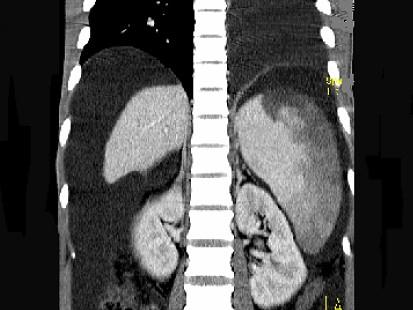

问题 患者男,29岁,乙肝病史10余年,腹胀,有移动性浊音,影像检查如图,最全面的诊断是 ( )

选项 A.肝硬化 B.肝硬化腹水 C.肝硬化腹水、脾梗、胆囊结石 D.大网膜膈下间位及脾梗 E.胆结石及脾梗

答案 C